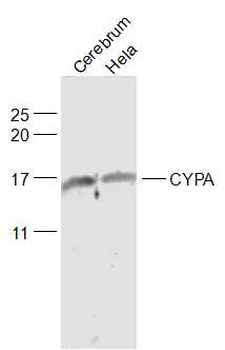

10 μg, 100 μgCYPA Rabbit Polyclonal Antibody [orb100498]

FC, IF, IHC-Fr, IHC-P, WB

Bovine, Canine, Porcine, Rabbit

Human, Mouse, Rat

Rabbit

Polyclonal

Unconjugated